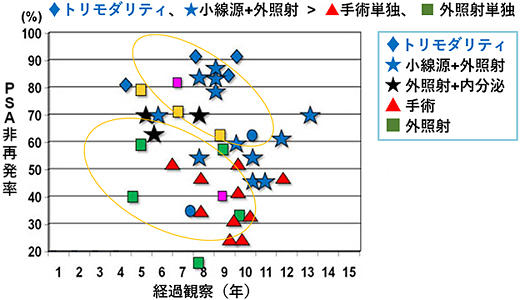

高リスクがん

高リスクがんの場合、10年で考えれば◆トリモダリティや★小線源+外照射は、▲手術単独や■外照射と比べ、※PSA非再発率は高い傾向があります。

※臨床的再発の前にPSAのみの持続的な上昇が認められ、カットオフ値以上になること

高リスクがんに対する治療は、手術、放射線治療いずれも単独での成績は大きな差がなく、いずれも治療も※生化学的再発率が比較的高く、必ずしも良好な成績とは言えないのが現状です。

※臨床的再発の前にPSAのみの持続的な上昇が認められ、カットオフ値以上になること

トリモダリティ療法の効果は?

高リスクがんに対する治療効果